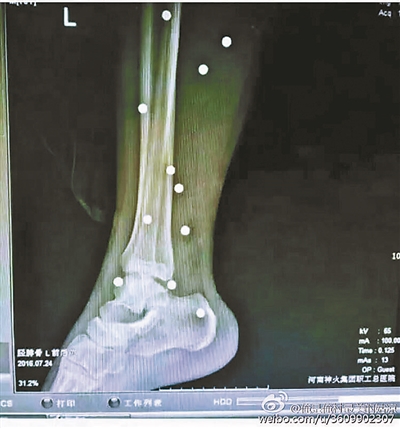

傷者體內(nèi)取出的鋼珠

爆炸導(dǎo)致鋼珠遍布傷者身體各處

黃明的伯伯對北青報(bào)記者表示,由于黃明直接踩到了爆炸物,所以傷情最為嚴(yán)重,“他的腿被炸斷,身體內(nèi)被炸進(jìn)了40多顆鋼珠。手術(shù)后已經(jīng)從體內(nèi)取出29顆鋼珠,還有十多顆鋼珠沒有取出來?!备鶕?jù)黃明的入院記錄,他全身有多處爆炸傷,且全身多處異物存留。

爆炸發(fā)生時(shí),陳浩的位置與黃明靠得很近,因此也受傷較重。他告訴北青報(bào)記者,經(jīng)過10多個(gè)小時(shí)的手術(shù)后,醫(yī)生從他身體里取出了12顆鋼珠。目前,他和黃明兩人經(jīng)過手術(shù)后,已從重癥監(jiān)護(hù)室轉(zhuǎn)至普通病房。其余三人中,陳剛的臀部受傷,當(dāng)天晚上在醫(yī)院清理完傷口后便回了家,而同行的兩名女生身上有一些擦傷。